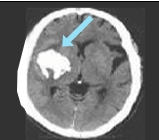

뇌출혈

뇌출혈은 성인의 65% 미만과 어린이의 5%에서 발생하며, 어린이에 비해 성인에서 더 흔합니다.

주요 원인

약한 대체 혈관의 파열, 미세동맥류 또는 기타 동반된 혈관 기형이 원인으로 여겨집니다.

어린이와 성인에서의 차이점

어린이에 비해 성인에서는 모야모야병의 진행이 느리고 상대적으로 안정적이지만, 뇌출혈이 발생하면 예후가 좋지 않을 수 있습니다.